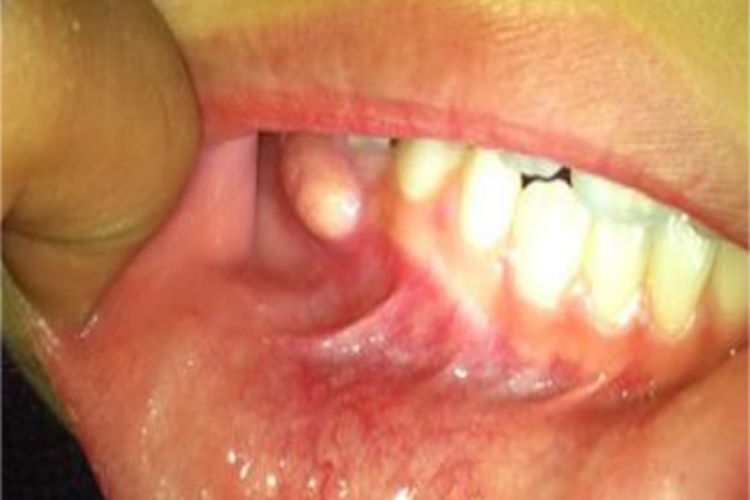

根尖周炎可累及牙龈,局部可出现凸起的脓包,大小不一,表面可为黄白色,质地较软。

根尖周炎累及牙龈时,可表现为异常凸起的脓包,大小不一、形状并不规则,表面可为黄白色,内含脓性液体,质地较软,触之有波动感。